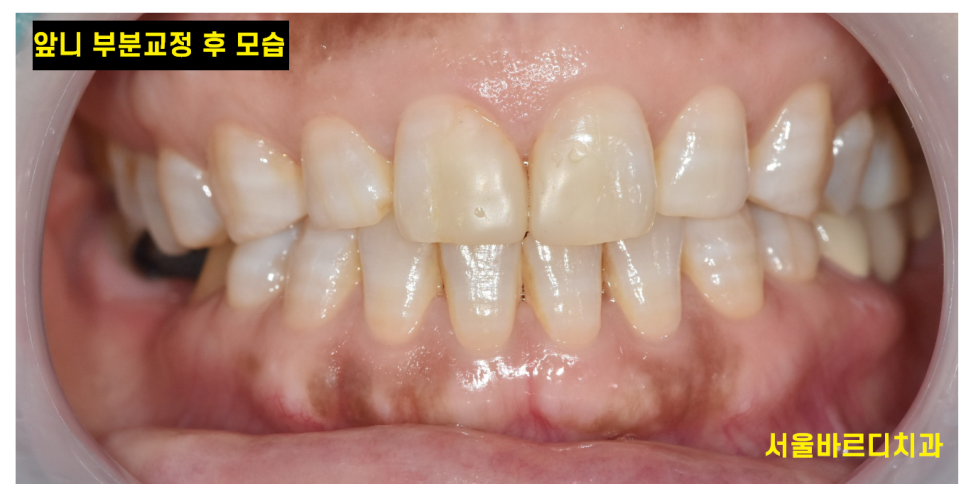

앞니 사이 틈이 없어졌죠~?

공간이 메워지면서 음식물이 끼는 등의 불편함도 사라지시겠어요.

아래 치아가 없는 부분은 임플란트 치료중이신데

앞니만 교정하기 때문에 임플란트 치료중에도 받으실 수 있습니다!